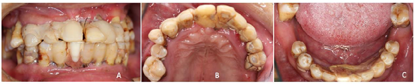

②上颌牙槽嵴黏膜翻瓣,清创炎性软硬组织,平整牙槽嵴顶骨嵴,在自由手操作下分别于12、15、22、25区植入4枚Nobel种植体,旋入复合基台,其中12、15、22区选择植入Nobel Speedy4.0x13mm种植体,25区选择Nobel Active4.3X11.5mm种植体,四颗种植体均利用鼻底皮质骨加强固位,初期稳定性均达到35N.cm(图5)。

③同上颌方法,平整牙槽嵴后于右下颌42、45区分别植入Nobel Speedy4x13mm种植体,均获得35N.cm的初期稳定性,左下颌区牙槽骨骨缺损明显(图6A),延期种植。45区为倾斜植入,放置30度复合基台,42放置球基台(图6B)。下颌种植术后拔除了原预留用作可摘义齿基牙的38、48。下颌过渡义齿利用植入的2枚种植体辅助支持固位,制作种植覆盖义齿过渡修复体(图7)。